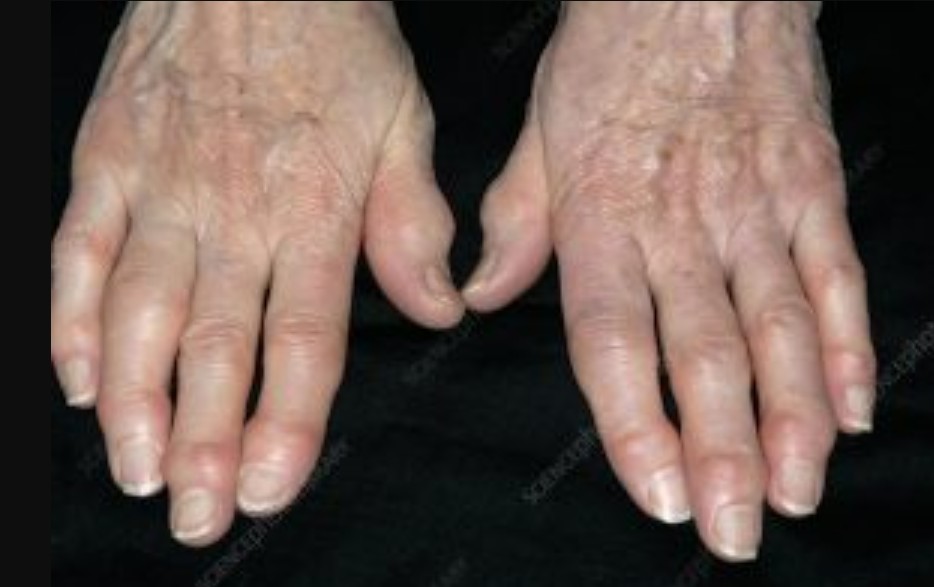

【本報訊】很多人誤以為手指關節變形就是類風濕性關節炎,其實在年紀大的患者造成手指關節變形更常見的原因,是手部退化性關節炎。手指退化性關節產生的原因是多面向的,常見因子有遺傳、女性、年長者、更年期後、肥胖、工作反覆勞動手指關節。

全身上下的關節都有罹患退化性關節炎的機會。除了膝關節、髖關節退化外,手部的退化性關節炎也很常見,尤其以手指的遠端指間關節和大拇指的掌指關節、掌腕關節最常發生。

手指疼痛最常發生在天氣濕冷、關節活動時,病況嚴重時可能會有關節局部發炎出現紅熱腫,變形後會出現關節活動困難。 在手部退化性關節炎中,有一部份患者特別嚴重,且惡化較快,容易造成關節變形與侵蝕,又稱為侵蝕性手部退化性關節炎。退化性關節炎沒有辦法根治,要讓手部有適當的休息,適時熱敷、按摩等,一旦感覺關節疼痛,就應該立即休息。